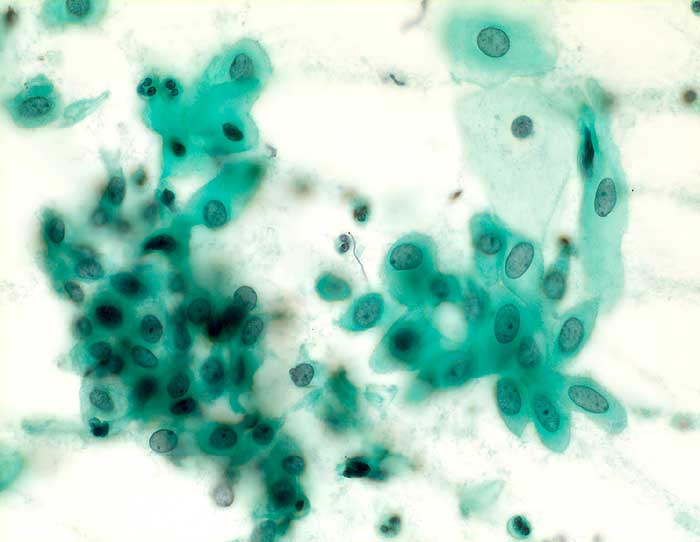

PathoPic ID 6063 - Plattenepithelmetaplasie

Plattenepithelmetaplasie

Metaplasie / Heterotopie

Portio

Genitalorgane, weiblich

Portio: rhombenförmige und leicht abgerundete unterschiedlich ausgereifte metaplastische Plattenepithelien mit milchglasähnlichen Kernen bilden einen mosaikartigen Verband.

Zytologie

400